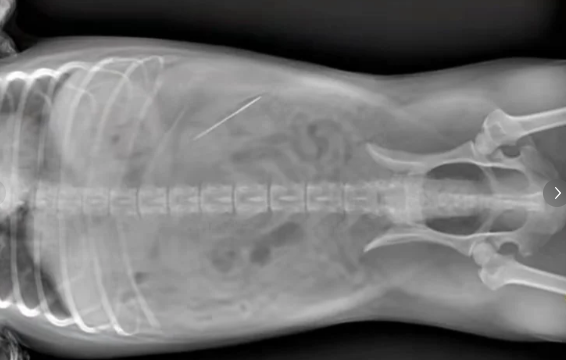

宠物医院院长徐洪齐用DR数字影像检查,果然在泰迪犬的胃里发现了一根缝衣针。徐院长决定用内窥镜给泰迪犬取针。他先把泰迪犬全身麻醉,后用内窥镜探查缝衣针位置,再用活检钳钳住缝衣针。经过十几分钟努力,终于将缝衣针取出。